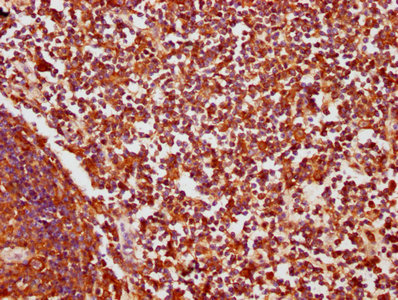

• IHC image of CSB-PA005934LA01HU diluted at 1:200 and staining in paraffin-embedded human lymph node tissue performed on a Leica BondTM system. After dewaxing and hydration, antigen retrieval was mediated by high pressure in a citrate buffer (pH 6.0). Section was blocked with 10% normal goat serum 30min at RT. Then primary antibody (1% BSA) was incubated at 4°C overnight. The primary is detected by a biotinylated secondary antibody and visualized using an HRP conjugated SP system.